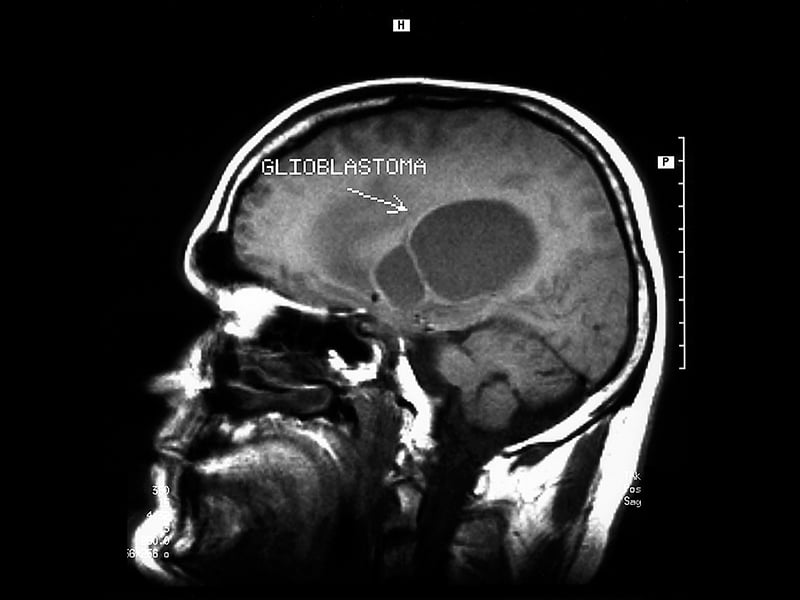

During a magnetic resonance imaging scan, atoms in the patient's body are exposed to a strong magnetic field. The technologist applies a radiofrequency pulse to the field, which knocks the atoms out of alignment. When the technologist turns off the pulse, the atoms return to their original position. In the process, they give off signals that are measured by a computer and processed to create detailed images of the patient's anatomy. Medical radiation isn't used in MR procedures.

Magnetic resonance image of head / Image © ASRT

Magnetic resonance image of head